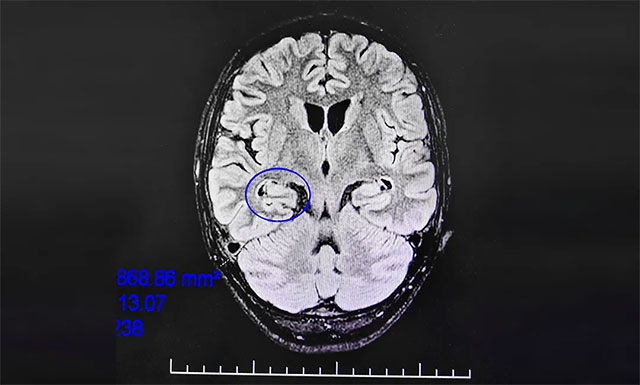

▲ 通過系列檢查最終明確患者致癲灶

腦電監(jiān)測(cè)崔麗華主任根據(jù)腦電圖監(jiān)測(cè)分析指出,患者雙側(cè)有癲癇波,右側(cè)較為嚴(yán)重。磁共振檢查,患者右側(cè)顳葉、海馬結(jié)構(gòu)代謝異常。既往史顯示,患者1歲時(shí)有頭部壓傷及缺氧窒息病史。

該患者經(jīng)系統(tǒng)內(nèi)科藥物治療不佳,確診為藥物難治性癲癇,經(jīng)過系列檢查最終明確患者致癲灶位于右側(cè)顳葉、右側(cè)海馬。手術(shù)指征明確,未見明顯手術(shù)禁忌癥。